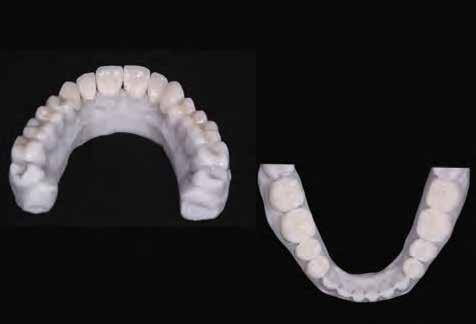

9. ábra: Digitális mosolytervezés. 11-12. ábrák: Az elkészült koronákat (1.3-1.1,

2.1-2.3),

valamint a héjakat (1.7-1.4,

4.1-4.7)

fényre kötő adhezív rendszerrel rögzítettük a pillérfogakhoz (Futurabond U and Bifix QM). 10. ábra: A végleges héjakat és koronákat Ceramill Mind tervező program segítségével digitálisan terveztük meg, majd frézgép segítségével (CeramillMotion 2, lithium-diszilikát tömbökből (VITABLOCS TriLuxe forte) faragtuk ki. 13-14. ábra: A végleges pótlások átadása után készült felvételek.

A már előzetesen preparált felső frontfogak csiszolt csonkjainak megtartottuk az eredeti formáját. Az alsó és felső őrlőfogak preparációja nem volt szükséges (1.7-1.4, 2.4-2.7, 3.7-3.4, 4.4-4.7), az alsó kismetsző fogakat minimál invazív módon készítettük elő. Az előkészítést követően új digitális lenyomat készült. Az így kapott digitális adatokat továbbítottuk a fogtechnikai laboratóriumba (9. ábra). A virtuális modellt ezek alapján hozták létre (AnatomicLab), és a minta elkészítéséhez szükséges STL fájlt továbbították egy háromdimenziós nyomtatóra (SolFlex 650, VOCO), amely segítségével elkészítették az új mintát (V-Print model, VOCO).

A végső restaurátumokat (héjakat és koronákat) Ce-

ramill Mind tervező program segítségével (AmannGirrbach) digitálisan megtervezték, majd frézgép segítségével (CeramillMotion 2, AmannGirrbach) li thium-diszilikát tömbökből (VITABLOCS TriLuxe forte for CeramillMotion 2, AmannGirrbach) kifaragták (10. ábra). Miután a fogpróba során ellenőrizték és megfelelőnek találták a pótlások széli záródásának a pontosságát, valamint az elkészült restaurátumok esztétikai megjelenését, ezután egy ajak- és szájterpesz került felhelyezésre (OptraGate, IvoclarVivadent).

A koronákat (1.3-1.1 és 2.1-2.3) és a héjakat (1.7-1.4, 2.4–2.7, 3.7-3.1, 4.1–4.7) fényrekötő adhezív rendszerrel rögzítették a pillérfogakhoz (Futurabond U ésBifix QM, VOCO). A polimerizációhoz egy nagy teljesítményű LED polimerizációs lámpát használtak (Celalux 3, VOCO), (1112. ábrák).